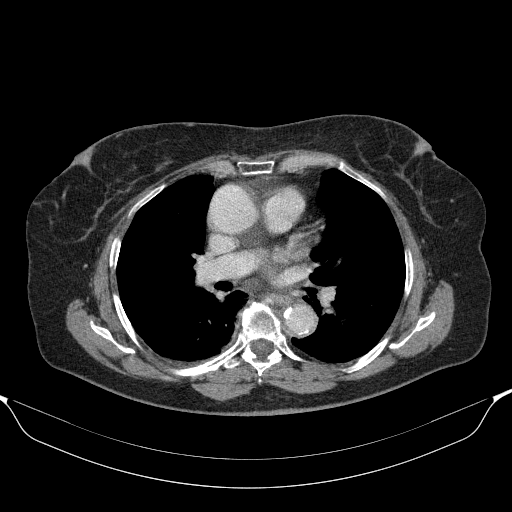

Original VENOUS CT scan

Full window (WL 1023.5, WW 4095 β†’ Low βˆ’1024, High +3071)

Actual HU range: [-1024.0, 1314.0]

Lung window (WL -600, WW 1500 β†’ Low βˆ’1350, High +150)

Actual HU range: [-1024.0, 150.0]

Mediastinum window (WL 40, WW 400 β†’ Low βˆ’160, High +240)

Actual HU range: [-160.0, 240.0]